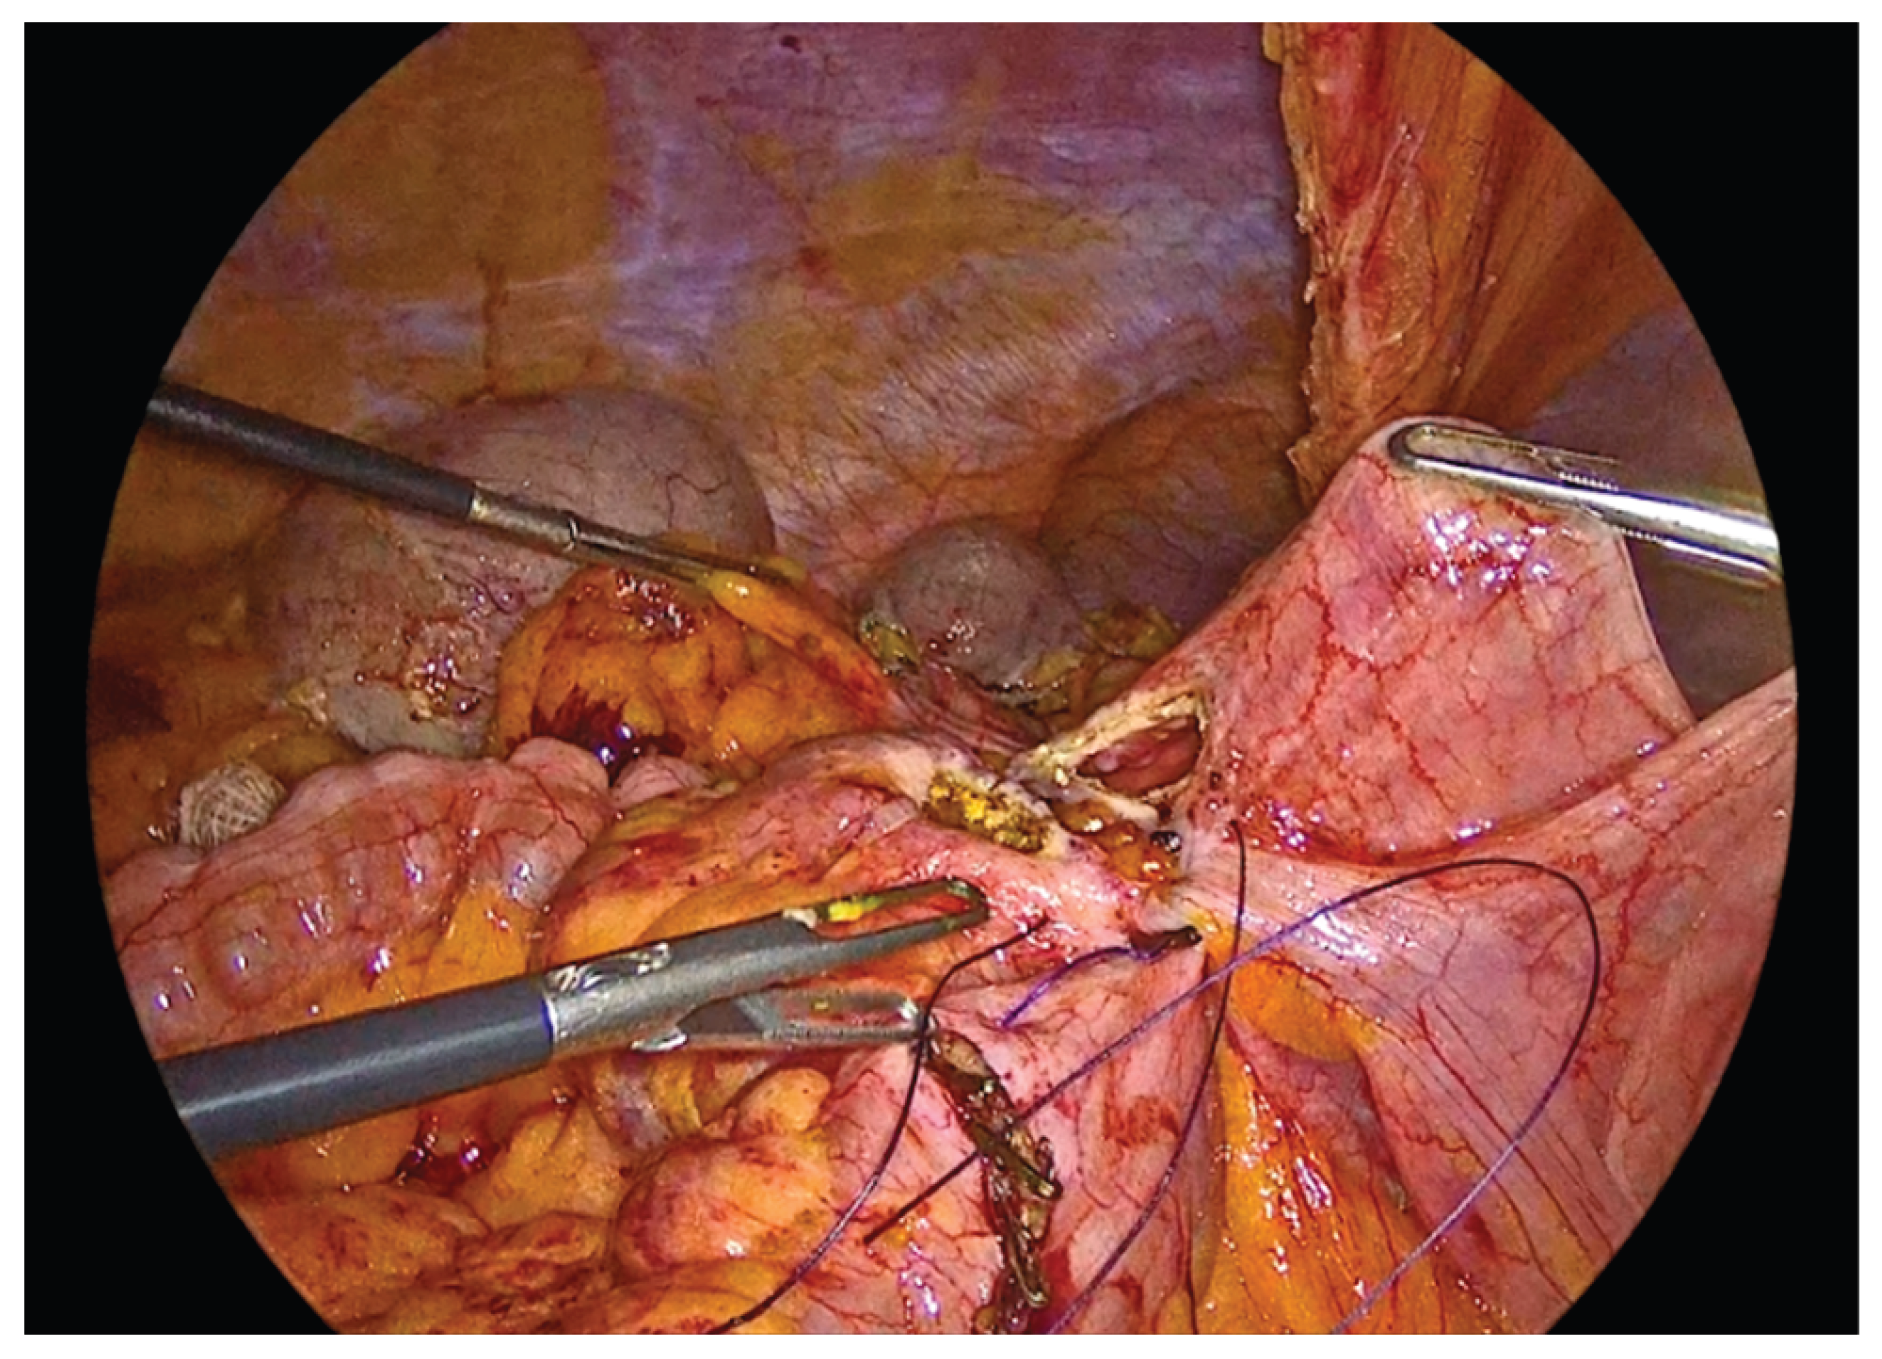

The anastomosis begins with a continuous seromuscular layer using a barbed 3-0 non - absorbable suture, extending for approximately 8 to 10 cm, providing reinforcement and support to the anastomosis.

Figure 6. Side to side isoperistaltic sutured alignment of transverse colon with ileum.

Preprints 195043 g006

Enterotomies are subsequently created on the antimesenteric borders of both bowel segments, at approximately 1 cm from the outer suture line, with a length of 3 to 4 cm.

Figure 7. Enterotomies of bowel ends.

Preprints 195043 g007